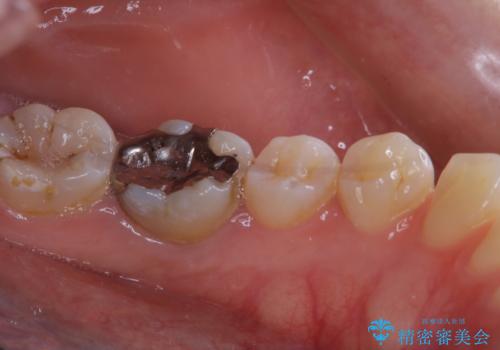

- これからインビザラインでのマウスピース矯正が始まるので、歯石取りをしてほしいとのことでした。

PMTC60分コースを行いました。

プラーク(細菌の塊)や歯石がたまると歯の表面はザラつきいてきます。そのザラつきは歯周病や虫歯菌の棲家となります。そのまま放置すると、歯肉が腫れてきたり、歯肉から出血したり、口臭が強くでたりします。とくに歯肉の境目は、歯磨きで汚れを除去することが難しく、プラーク(細菌の塊)や歯石が溜まりやすい場所です。

歯並が、がたついている場合はなおさら汚れが溜まりやすいです。矯正治療前や矯正中、定期的にPMTCをすることで、矯正治療中の歯肉トラブルを防ぐことにつながります。